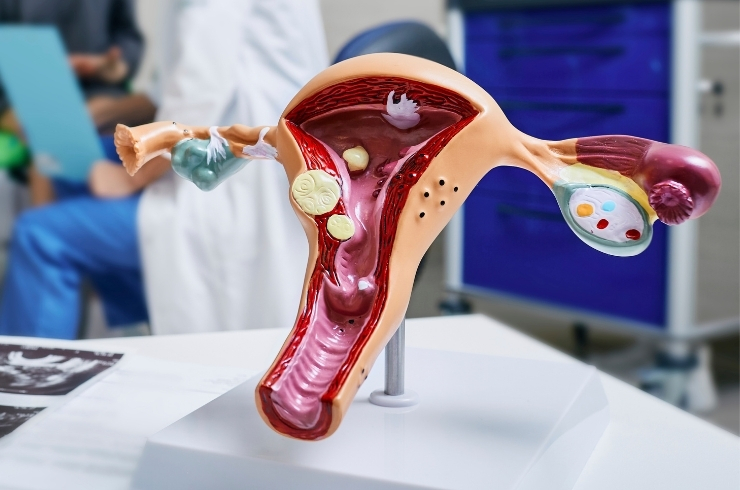

Women’s healthcare including pregnancy care, high-risk obstetrics, deliveries, and gynecological treatments with expert supervision.